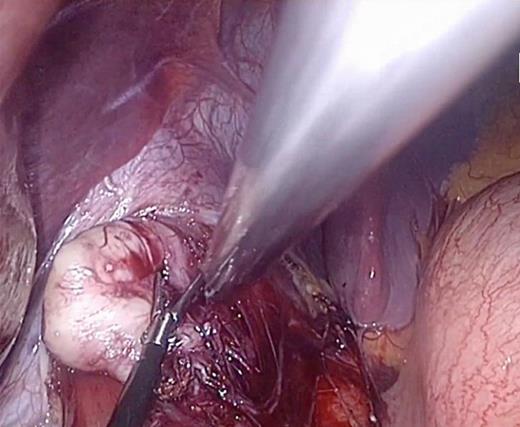

After dissection of the oesophago-gastric ligament and reduction of herniated stomach into the abdomen, the lesion in the distal oesophagus was identified (Fig. 1). It was enucleated leaving the oesophageal and gastric mucosa intact. The remainder of the procedure then continued as planned and was uneventful. The patient had no concerns postoperatively and was discharged home within 24 h. The lesion was sent for histopathological analysis and a plan for follow-up was organized.